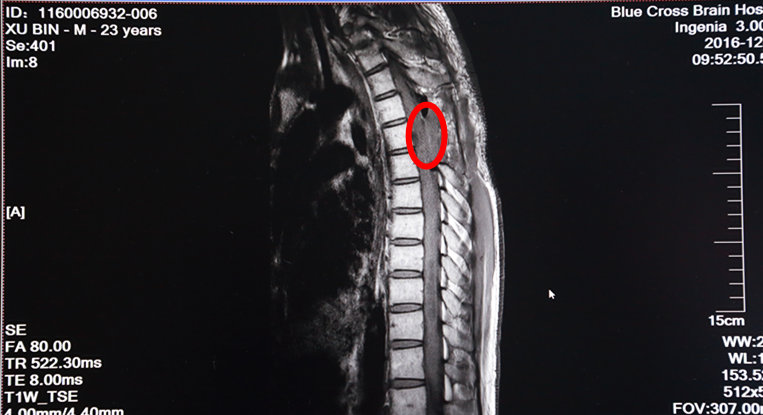

术后MRI增强扫描:红圈内肿瘤物已消失

次日,手术进行。术中,在全麻下打开硬脊膜,手术显微镜下,脊髓表面见大量迂曲的血管团,选择血管相对稀少而功能不是很重要的区域切开薄如薄纸的脊髓,小心沿肿瘤边缘分离并逐次切断供应肿瘤的血管,顺利地完成了肿瘤的全切除。术后增强MRI示肿瘤已经全部切除了。